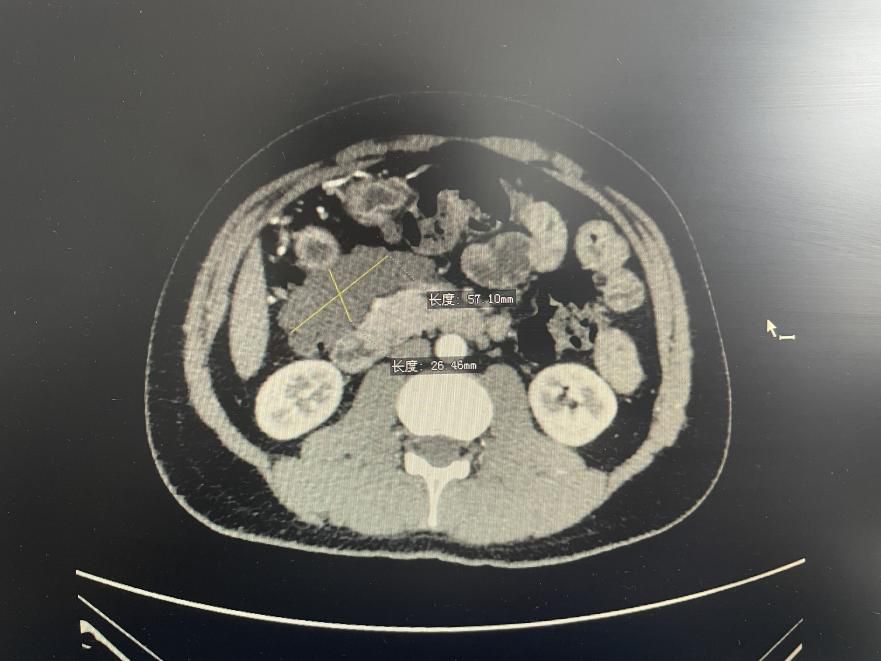

患者为20多岁,因为反复上腹部胀痛,CT检查后发现上腹部12x10cm大小囊性肿物,入院治疗。成年腹腔内淋巴管瘤国内较少见、发生率极低。因患者肿瘤生长的特殊部位恰好位于位于小网膜囊内,胃后壁、脾门和胰腺之间,与胰腺关系密切。患者消化道肿瘤指标正常,有轻度消化道压迫症状,周围组织多,涉及多个脏器,且有外溢造成腹腔内播散的可能,手术难度极大。

分管外科张卫国副院长率领普外科刘峰主任,胡占军主任医师,刘晓龙医师,陈敏护士长,麻醉科白宏主任,郝美玲、李晓波副主任,田芳护士长,影像科主任王朴在,张志强副主任组织了MDT(多学科协作)团队,经过对患者病情的认真讨论研究,分析患者囊肿边界清楚,CT未见明显附壁结节和小囊性改变,考虑网膜或者淋巴来源的可能性大。